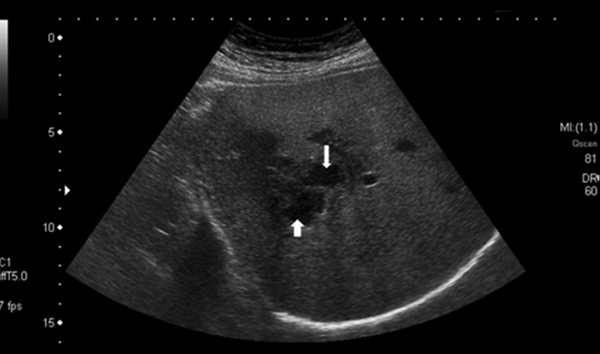

Xét nghiệm công thức máu ghi nhận, bệnh nhân có tình trạng tăng bạch cầu ái toan, xét nghiệm huyết thanh chẩn đoán Fasciola spp. dương tính. Kết quả siêu âm cho thấy có ổ áp xe ở gan, kích thước 5×8cm ở thai phụ 16 tuần và 7×8,4cm ở thai phụ 28 tuần.

Hình ảnh áp xe gan do sán lá gan lớn trên siêu âm. Ảnh: BVCC.